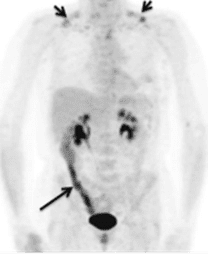

Por este motivo, el uso de 18F-FDG se usa en PET para la detección de múltiples tipo de tumores, ya que estos consumen una gran cantidad de azucares para su rápido crecimiento; infecciones multisistémicas inflamatoria, que también necesitan un alto consumo de glucosa; enfermedades metabólicas en cerebro y pulmones, y por último para la detección de enfermedades cardiovasculares, como el infarto agudo de miocardio, ya que las células muertas del corazón no consumen glucosa y, por lo tanto, si no se observa este marcador en el corazón, se puede concluir la existencia de esta patología.